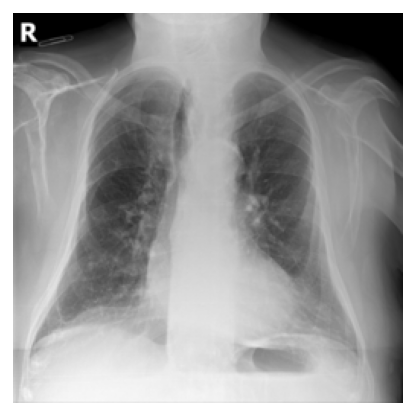

SparK reconstruction GradCAM: encoder attention during masked patch reconstruction

SparK encoder attention during reconstruction. The yellow box marks the target masked patch; the heatmap shows which visible patches were used to reconstruct it.

The reconstruction GradCAM shows that even for a single missing patch (yellow box), layer2 already draws on the right structural context, with layer3 and layer4 progressively narrowing in. Finetuning on only a handful of labeled examples means there is nothing to gain by adjusting layer2 further without a bigger risk of overfitting. That's why we unfreeze layer3+ for SparK.